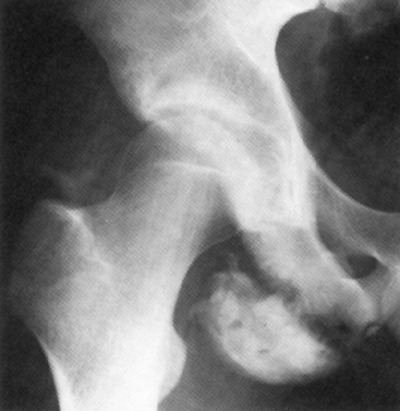

injuries seen in adolescents and young adults. Avulsion fractures occur

primarily between the ages of 14 and 25 years and account for

approximately 15% of pelvic fractures in children (228,229,230).

or eccentric muscle contraction, which occurs with rapid acceleration

or deceleration.

activities such as sprinting and jumping sports, as well as soccer and

football (228). The same mechanism that would cause a muscle or tendon strain in an adult may cause an apophyseal avulsion in an adolescent.

contraction of the sartorius as seen in jumping or running, from the

anterior inferior iliac spine (AIIS) due to overpull of the straight

head of the rectus femoris, and from the ischial tuberosity due to

forceful contraction of the hamstrings (Fig. 32.23).

Avulsions of the AIIS are often seen in participants of sports

![]() |

|

Figure 32.23

Avulsion fractures of the growing pelvis result from traction injuries where major muscle groups insert into or originate from apophyses about the pelvis. The abdominal and trunk muscles insert into the iliac apophysis (a). The sartorius originates from the anterior superior iliac apophysis (b). The direct head of the rectus femoris originates from the anterior inferior iliac apophysis (c). The iliopsoas inserts into the lesser trochanteric apophysis (d). The hamstrings originate from the ischial apophysis (e). |